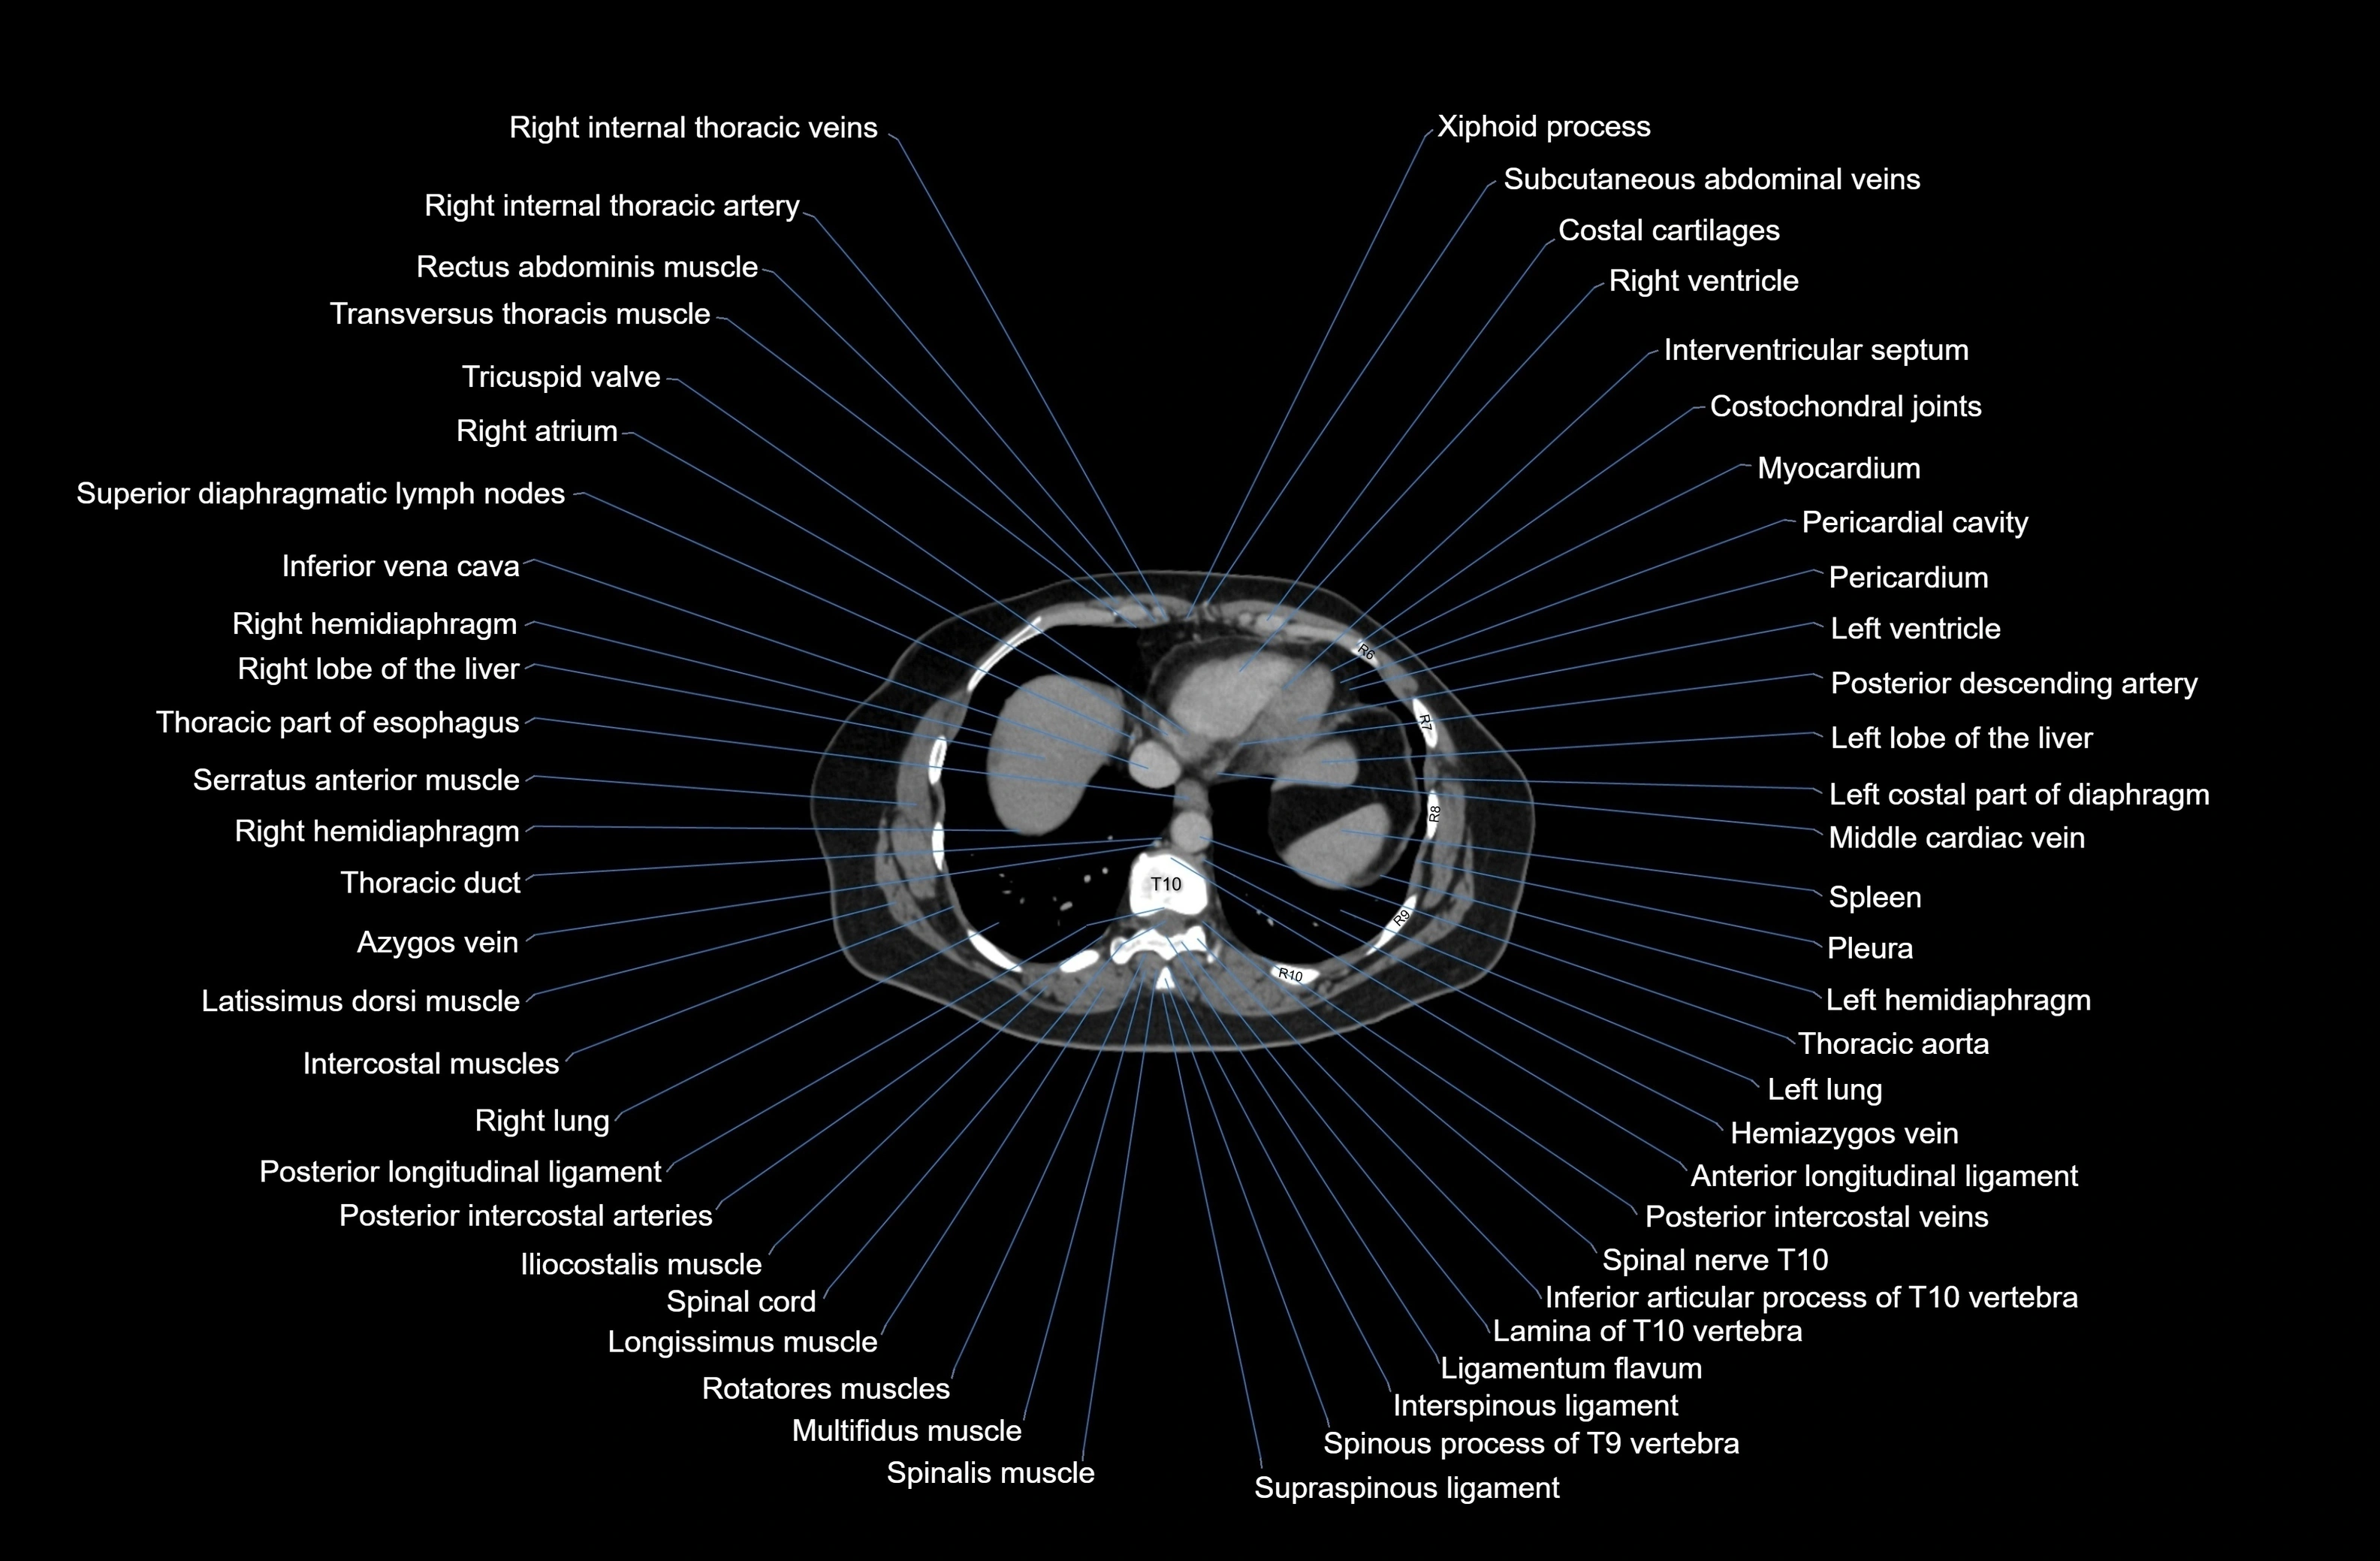

CT images